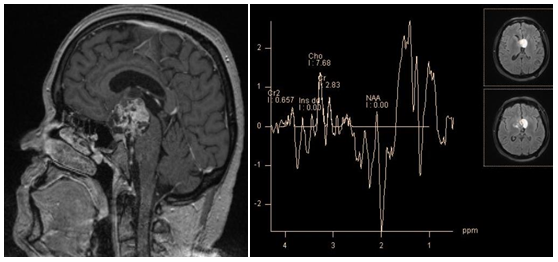

Tumefactive demyelinating lesions on conventional MRI may be indistinguishable from intra axial tumors. In this case, MR spectroscopy can provide useful information (Figure 2). Although the metabolite profiles of demyelination lesions in the acute phase and tumors may be similar, in general, tumors show higher concentrations of choline and myo-inositol. Still there is no consensus among authors.6 According to C. Majós et al. the ratio ≥ 0.9 of M-Ins/NAA and ≥ 1.9 CHO/NAA is strongly suggestive for tumors.7 According to other studies, the only reliable criterion in differentiate tumors from demyelinating lesions NAA/Cr ratio in the central areas of lesions. For demyelinating lesions average NAA / Cr ~2.4, for gliomas~0.9.8

Figure 2 Chronic tumefactive demyelinating lesion in the right Corona radiata. PRESS, TE 30 ms(a, b) PRESS, TE 30 ms, PRESS, TE 135 ms (c, d). Spectra of the lesion (a, c)in comparison with normal brain parenchyma on the opposite side (b, d). At short TE, concentrations of the main metabolites in the lesion seem normal, marked by high peaks Lac/Lip 1.3 ppm and Lip/MM 0.9 ppm. At intermediate TE lactate peak is absent, there is only a slight decrease of NAA, Cho and Cr concentrations are normal. This "benign" metabolite profile helps rule out tumor.